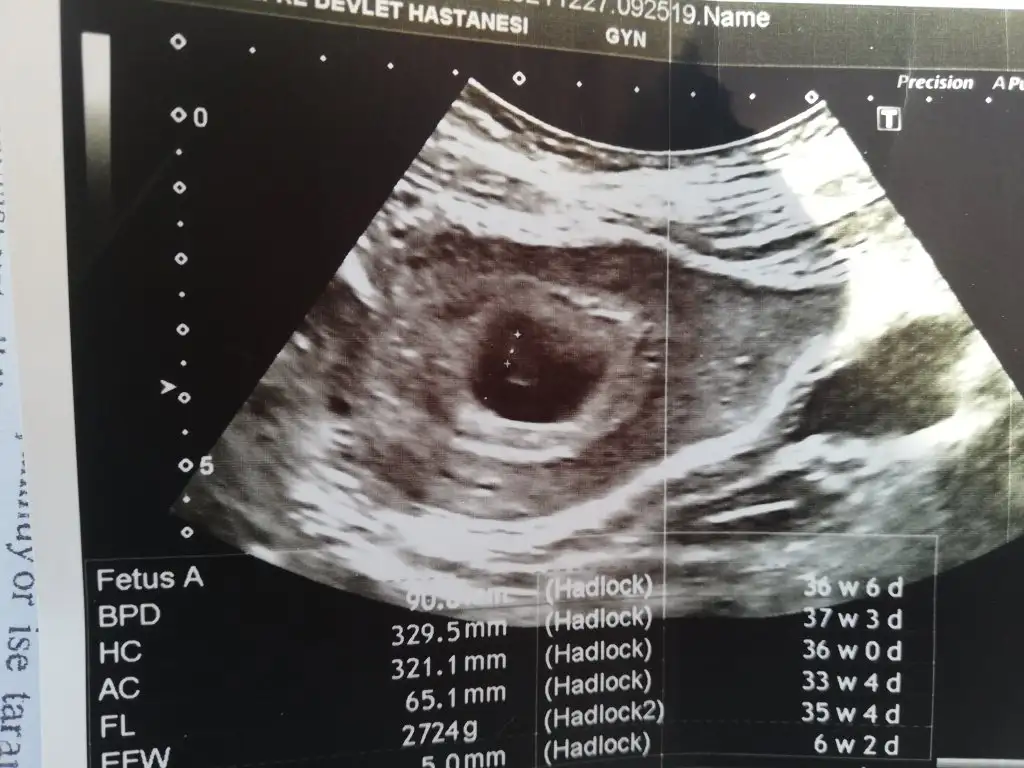

Eki Görüntüle 2977303